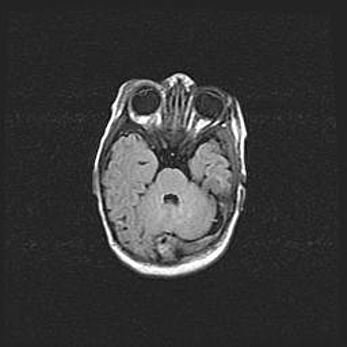

Неполная лизэнцефалия (пахигирия). Открытая гидроцефалия.

Возраст: 17 дней

Вес: 3110 г

Пол: мужской

Окружность головы: 33,5 см

Срок гестации: 35-36 недель

Лизэнцефалия—недоразвитие корковой пластинки и мозговых извилин в результате нарушения миграции нейронов коры. Поверхность мозговых полушарий гладкая. Микроскопически выявляется отсутствие нормальных слоев коры и скопление групп нейронов в подкорковом белом веществе.

Пахигирия—уменьшение числа вторичных извилин. В пораженном полушарии нервные клетки образуют толстый недифференцированный слой с неправильно расположенными нервными волокнами и группами гетеротопных клеток. Нервные клетки незрелые. Белое вещество истончено. При этом нередко аномально развит корково-спинномозговой путь.